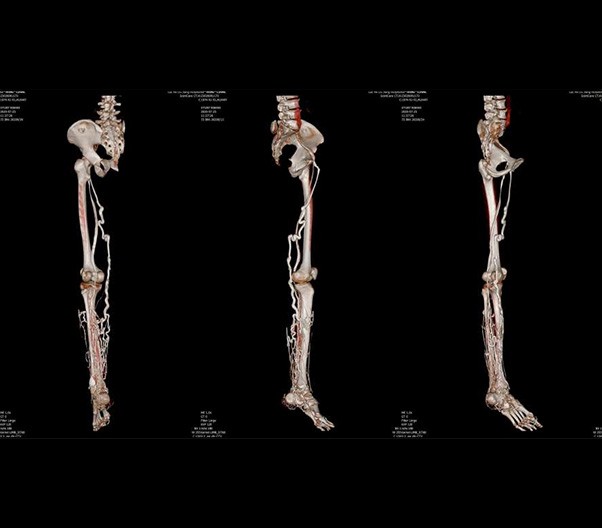

臨床畫(huà)廊